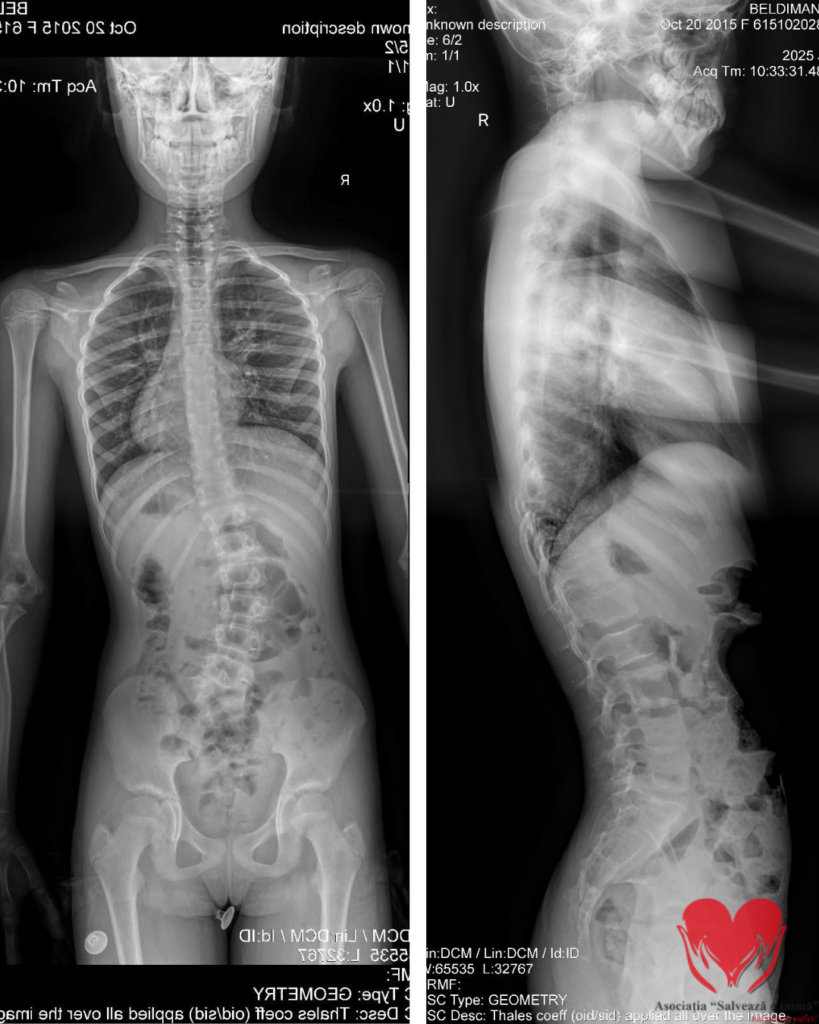

Eva Maria Raluca Beldiman are 10 ani. În fișa medicală scrie simplu: hemivertebră lombo-sacrată L5 stânga complet segmentată. În realitate, diagnosticul definește o poveste despre curaj, speranță și solidaritate.

La 5 ani, o radiografie pentru un obiect înghițit accidental a scos la iveală ceva neașteptat: coloana Evei nu creștea drept. Investigațiile ulterioare au confirmat scolioza toraco-lombară, cauzată de vertebra incomplet formată care împinge coloana să se deformeze progresiv.

Eva poartă corset Cheneau și urmează terapia Schroth. Merge la școală, zâmbește și își face temele. La exterior, pare un copil obișnuit, dar fiecare lună înseamnă o curbură care poate progresa fără intervenție chirurgicală – hemivertebrectomie prin tehnica Ruf-Harms. Această operație oferă șansa unei dezvoltări normale și fără dureri.